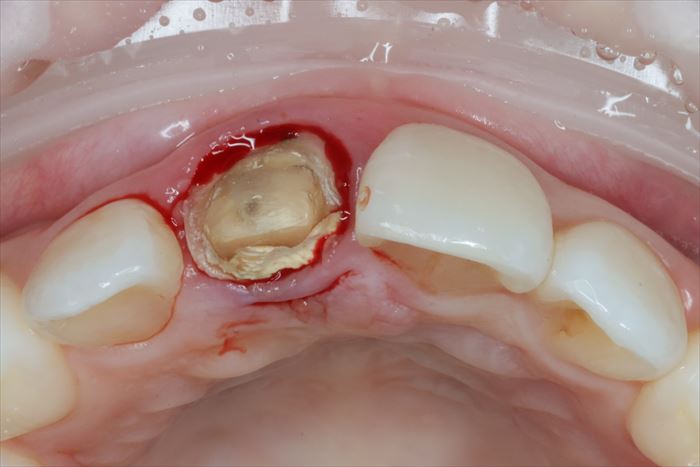

F・Kさんの初診時の状態です。

右上中切歯(右上1)に歯根吸収と炎症がありインプラント治療をご希望です。

過去に神経を取る治療(=根管治療)がなされており、残念ながら歯根の吸収が起こっています。

まずは現状の仮歯が外れました。

続いて支台築造と周囲の歯質が取れました。

まだ歯根が残っていますが歯肉が入り込んでいたことが判ります。